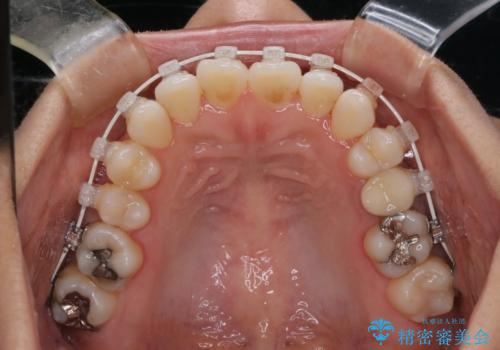

- 開咬を主訴に来院されました。前歯部に開咬、右側大臼歯部にクロスバイトが認められます。ワイヤー矯正の審美装置で治療し、ゴム掛けを行いながら噛み合わせを改善しました。

主訴である開咬と右側大臼歯部クロスバイトを改善でき、しっかりと噛むことができるようになりました。